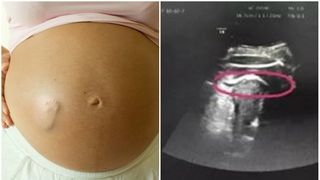

O femeie în vârstă de doar 34 de ani a murit la o zi după ce fetița pe care o născuse prematur a decedat. Băimăreanca, asistentă medicală, nu era vaccinată și a fost confirmată pozitiv COVID-19 la internare. Familia Cristinei acuza medicii Spitalului Județean de Urgență Baia Mare că i-ar fi spus despre decesul fetiței, direct și fără menajamente, iar aceasta ar fi suferit un șoc puternic care ar fi condus la deces.

Cristina era nevaccinată și gravidă în luna a 8-a. Ea s-a simțit rău, s-a dus la spital, a ieșit pozitivă în urma testării PCR și a născut de urgență prin cezariană în speranța că vă fi ok copilul, informează eMaramures.ro .

Din nefericire, după 3 zile, fetița născută...